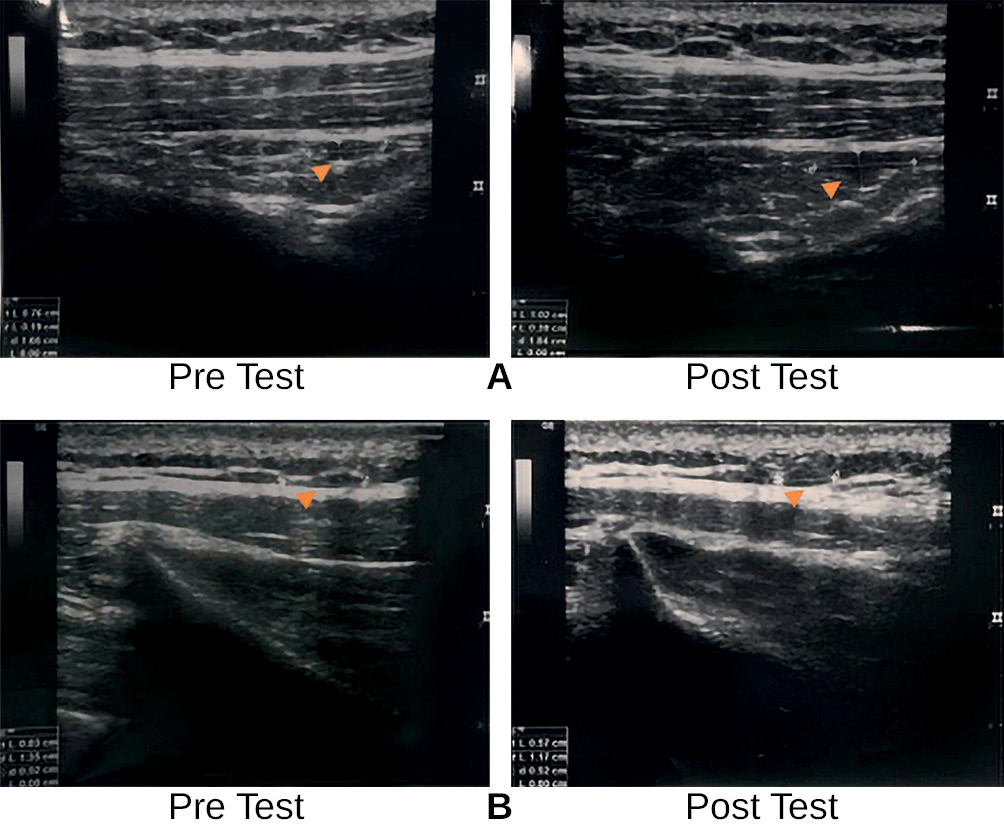

Similarly, the DFM group showed an increase in trigger point size, with a mean pre-test size of 1.00 ± 0.15 increasing to 1.30 ± 0.2 post-test. In this group, 4 participants experienced a reduction in size, while 12 showed an increase (Fig. 3). Unlike the DN group, the DFM group displayed significant changes in trigger point size according to statistical analysis (p < 0.05).

Fig. 3. Ultrasound Images of Neck Muscles Pre and Post Deep Friction Massage Showing Trigger Point Size Changes.

Note: A — presents ultrasonographic (USG) images of the neck muscles captured before and after the deep friction massage (DFM) intervention, showing an increase in trigger point size from 0.76 cm to 1.02 cm; B — displays USG images of the neck muscles obtained pre- and post- DFM, highlighting a reduction in trigger point size from 0.83 cm to 0.57 cm.